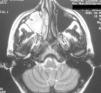

Paciente de 27 años de edad sin antecedentes de interés que ingresó procedente de urgencias por dolor retroocular de 5 días de evolución que se incrementaba con los movimientos oculares, asociado en las últimas horas a limitación del campo visual derecho. La exploración neurológica y el fondo de ojo fueron compatibles con la normalidad, a excepción del escotoma ya referido. El estudio campimétrico realizado puso de manifiesto una pérdida del campo visual derecho. En los estudios de neuroimagen —tomografía computarizada (TC) maxilofacial (fig. 1) y resonancia magnética (RM) cerebral, secuencias ponderadas en T1, T2, DP y flair(fig. 2)—, se objetivó lesión ocupante de espacio en el seno maxilar, frontal, celdas etmoidales y fosa nasal derechas. La rinofibrolaringoscopia confirmó una colección de moco y pus en las cavidades paranasales derechas. Con el diagnóstico de rinosinusopatía y neuropatía óptica por vecindad, se inició antibioterapia vía oral, que mejoró los síntomas de la paciente y normalizó el estudio campimétrico.